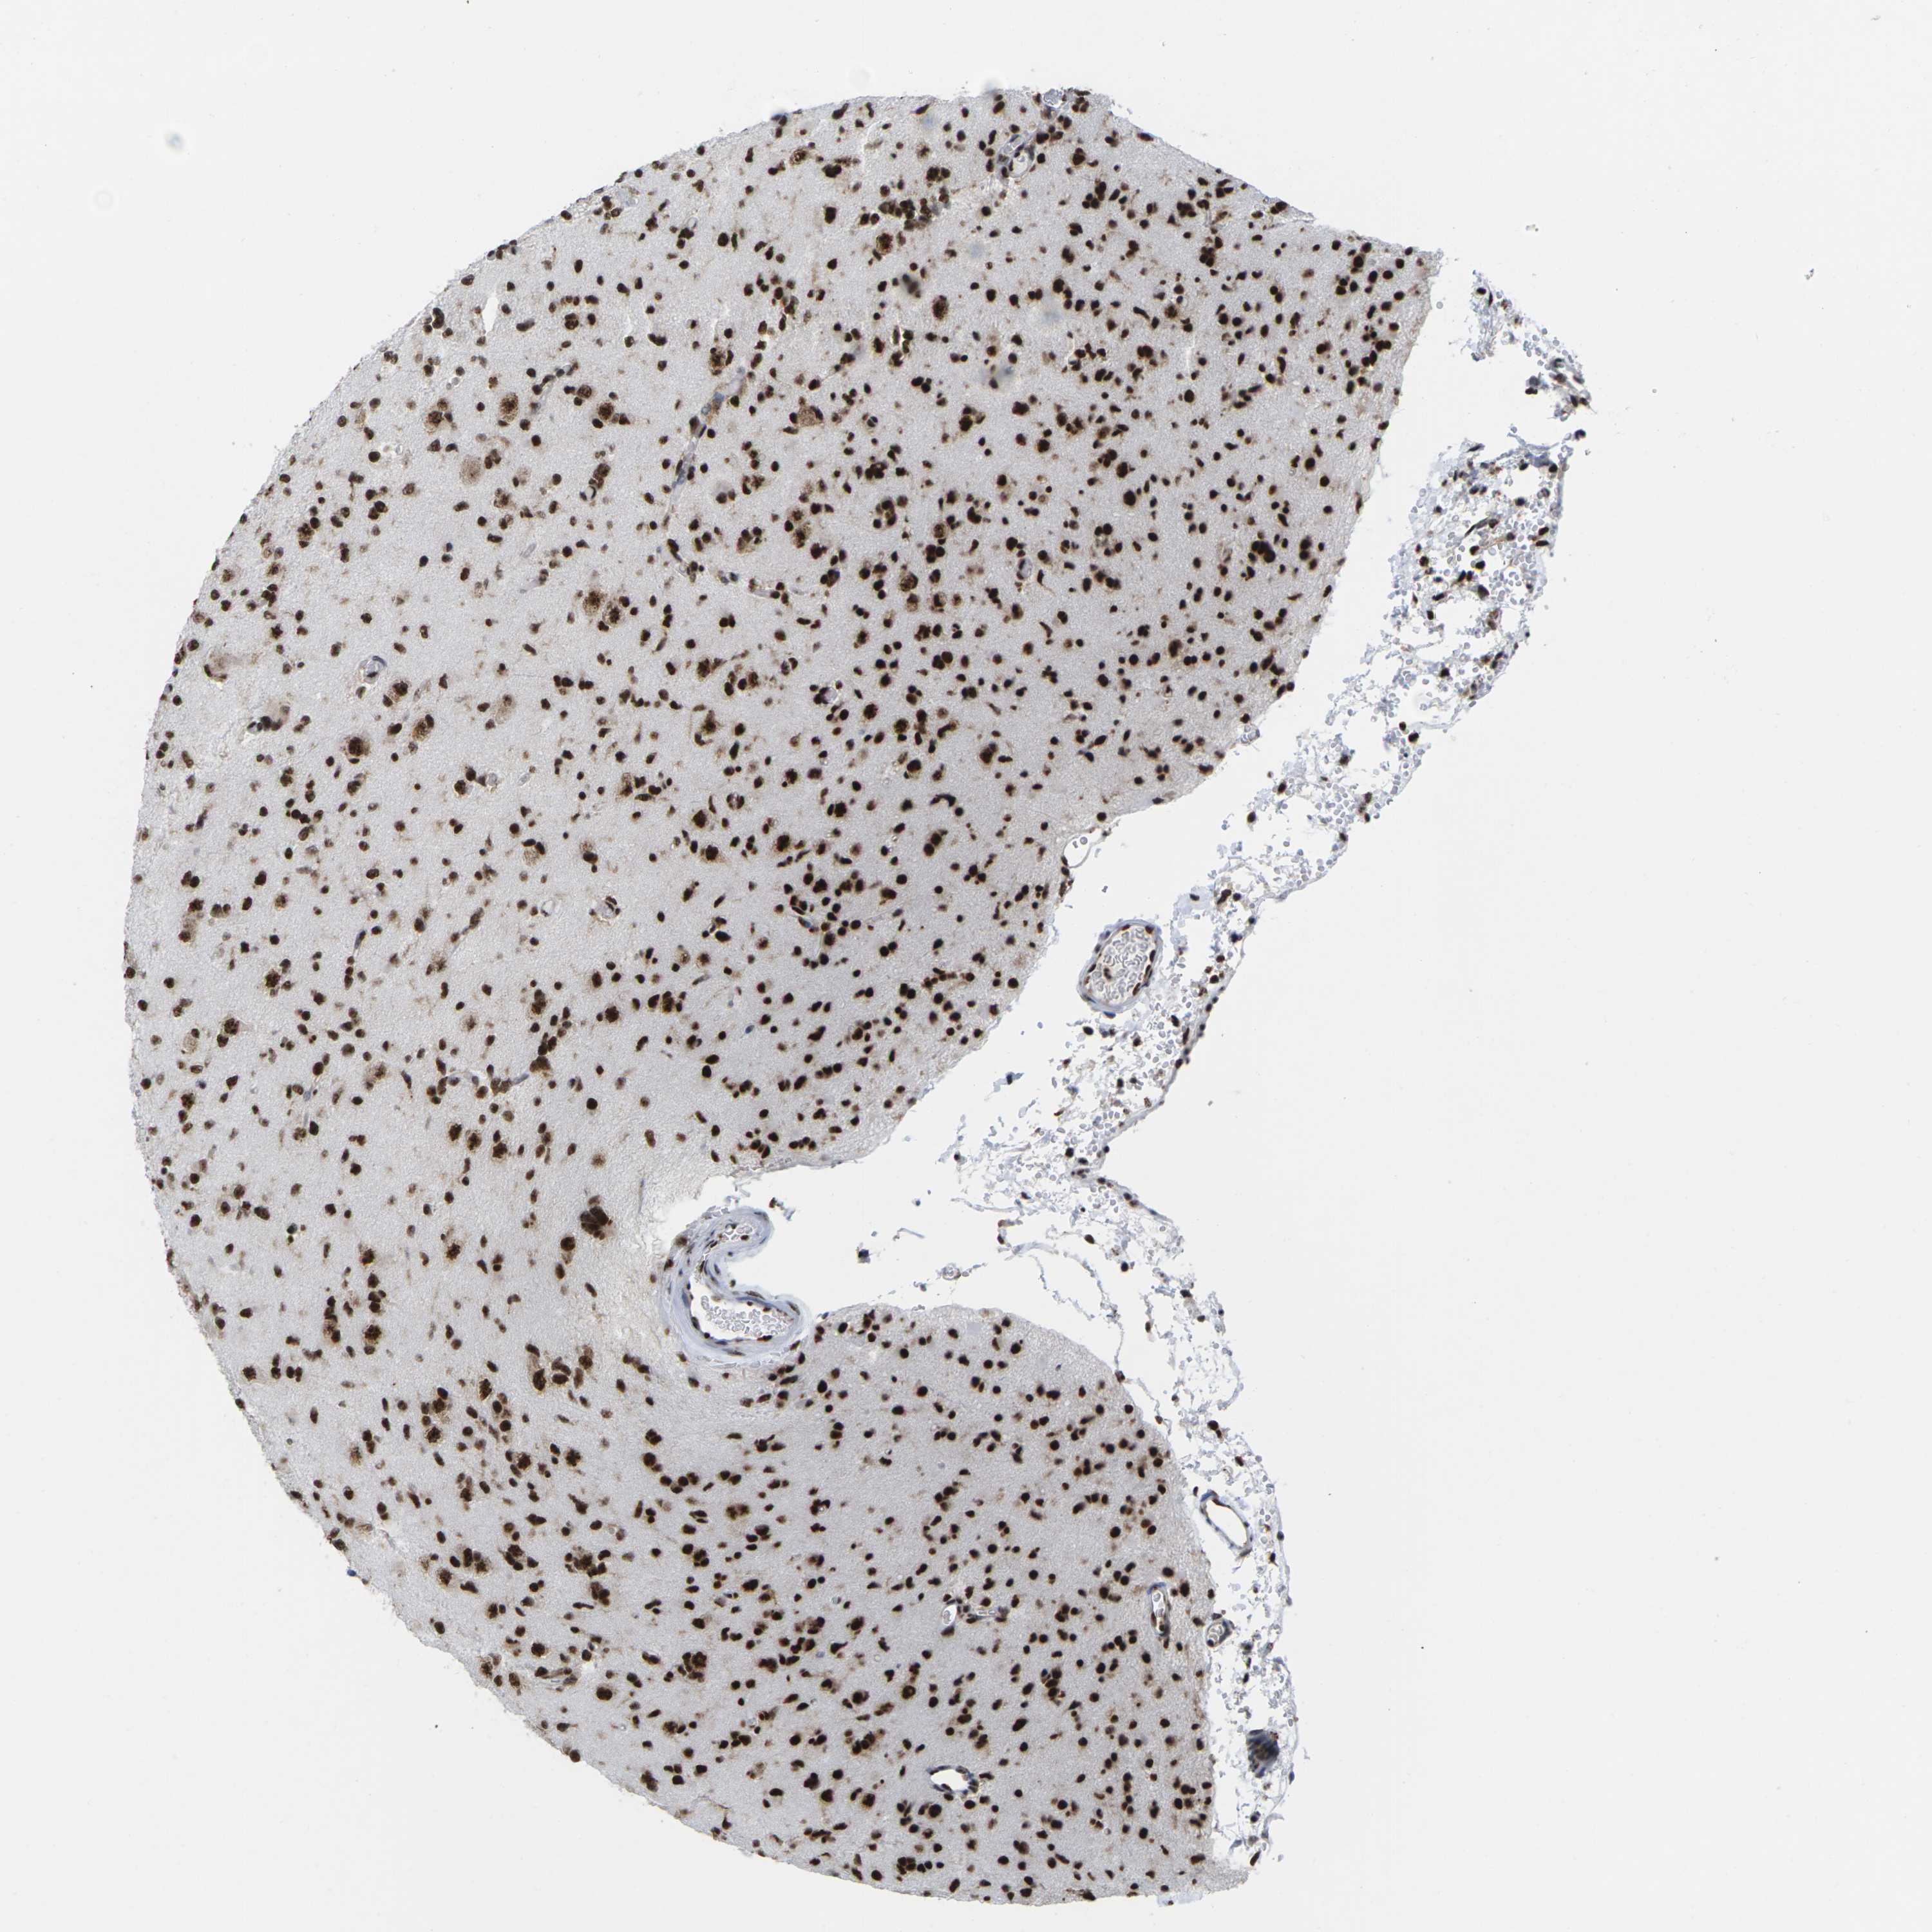

GLIOMA - Protein expressioni

A mouse-over function shows sample information and annotation data. Click on an image to view it in a full screen mode. Samples can be filtered based on level of antibody staining by selecting one or several of the following categories: high, medium, low and not detected. The assay and annotation is described here.

Note that samples used for immunohistochemistry by the Human Protein Atlas do not correspond to samples in the TCGA dataset.

Antibody stainingi

Antibody staining in the annotated cell types in the current human tissue is reported as not detected, low, medium, or high, based on conventional immunohistochemistry profiling in selected tissues. This score is based on the combination of the staining intensity and fraction of stained cells.

Each image is clickable and will lead to virtual microscopy that enables deeper exploration of all samples and also displays staining intensity scores, fraction scores and subcellular localization as well as patient and tissue information for each sample.

Antibody HPA043036

Antibody HPA047754

Antibody CAB015425

Staining

High

Medium

Low

Not detected

Intensity

Strong

Moderate

Weak

Negative

Quantity

>75%

75%-25%

<25%

None

Location

Nuclear

Cytoplasmic/membranous

Cytoplasmic/membranous,nuclear

Glioma, malignant, High grade

Glioma, malignant, Low grade

Glioma, malignant, NOS